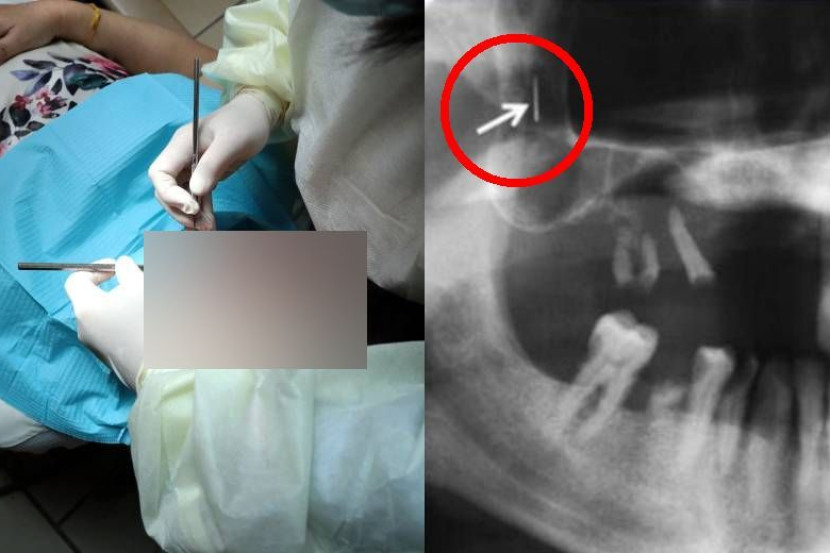

Cetakan X-ray menunjukkan jarum susuk ditanam di dalam rahang.

"Pesakit merupakan seorang wanita, usianya agak lanjut, boleh dilabelkan sebagai makcik. Ketika saya sedang periksa mulut makcik tu, saya sarankan dia untuk buat X-ray supaya boleh dapat gambaran lebih jelas.

"Tapi makcik tu cakap tak perlu sebab dia dah pernah buat X-ray dekat tempat lain sebelum ni. Maka saya pun tengok paparan X-ray mulut makcik tu melalui skrin telefon pintarnya. Saya terus perasaan ada sesuatu yang pelik dalam X-ray tu.

"Saya nampak ada jarum pada rahang kiri dan kanan makcik tu. Ini kali pertama saya jumpa benda macam ni, saya pun tanya dengan senior untuk minta penjelasan. Dia kata benda tu adalah 'susuk'. Saya dah ngeri waktu tu.